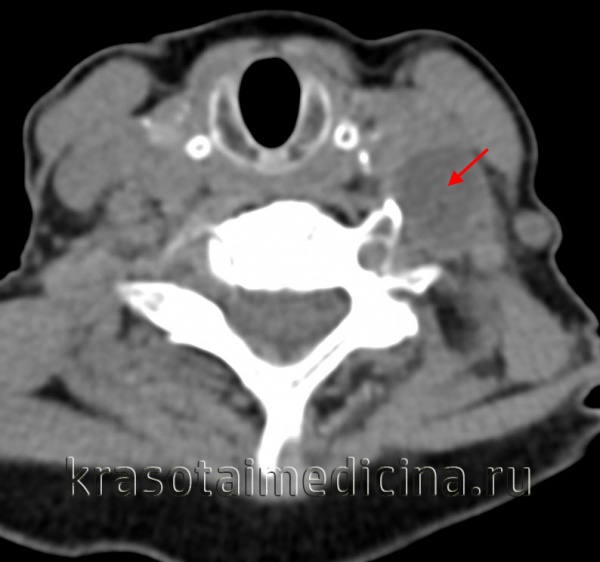

2. КТ при кисте щитоязычного протока:

• КТ с КУ:

о Гиподенсное кистозное образование шеи, расположенное срединно и накапливающее контраст в виде тонкого ободка:

- При инфицировании стенка кисты может накапливать контраст

- В редких случаях обнаруживаются перегородки

о Надподъязычная КЩЯП:

- Корень языка или задние отделы дна полости рта

о На уровне подъязычной кости:

- Срединно, обычно вплотную к подъязычной кости спереди

- Может выбухать в преднадгортанниковое пространство

о Подподъязычная КЩЯП:

- Погружена в подподъязычные мышцы=симптом «когтя»

- Более каудальные КЩЯП обычно располагаются парамедианно